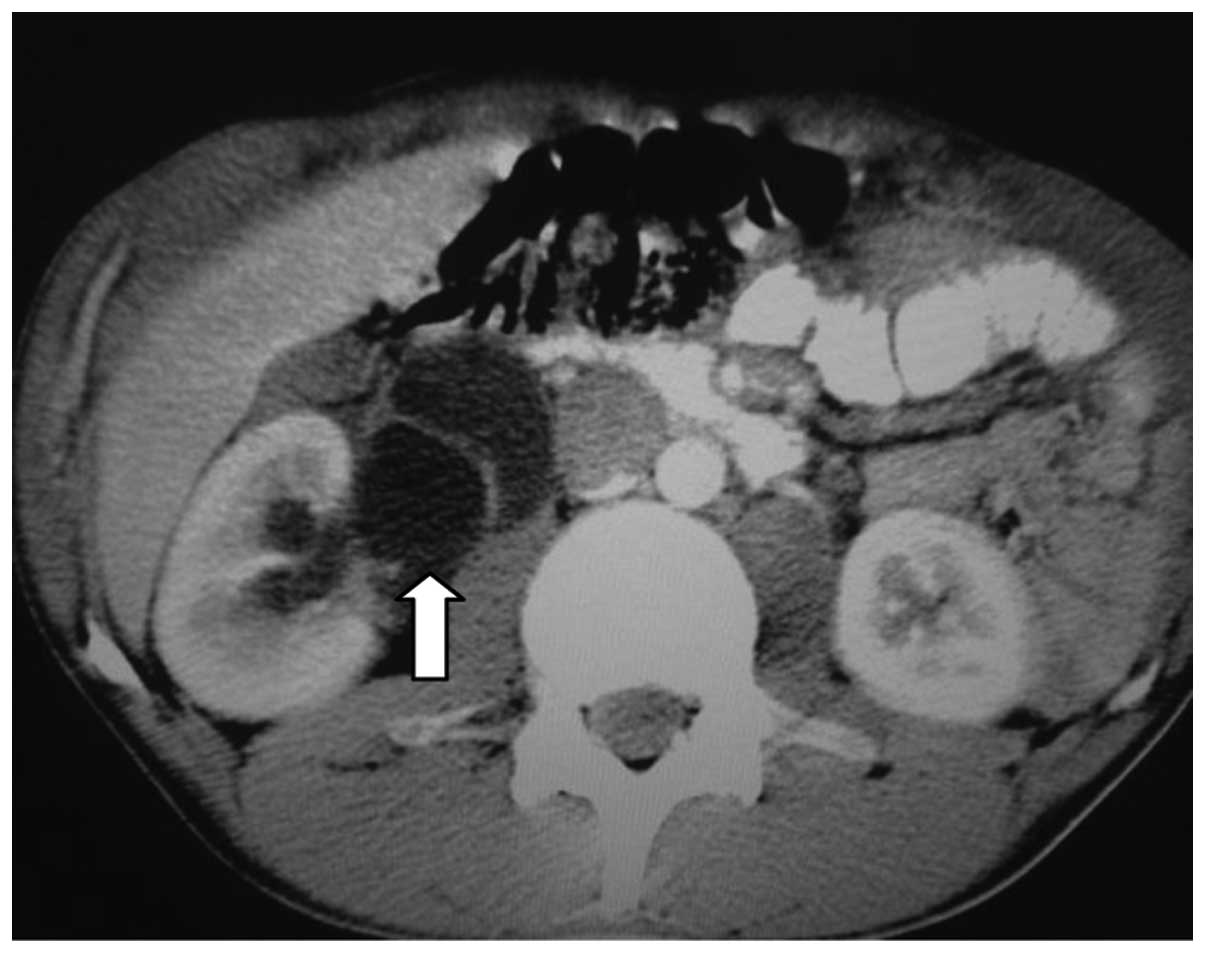

Computed tomography (CT) scans of the abdomen and pelvis revealed a heterogeneous, hypovascular pelvic mass measuring 7.6×6.8 cm (Fig. 1). The mass was located posteriorly and superiorly to the bladder, with thickening of the rectum and a right large hydronephrosis (Fig. 2). Additionally, colonoscopy identified extrinsic compression into the rectum. The differential diagnosis was of a lymphoproliferative lesion or retroperitoneal sarcoma. However, subsequent ultrasound-guided biopsy and histopathological analysis of the pelvic mass indicated a morphology compatible with a high-grade malignant neoplasm. It was characterized by groups of small cells featuring large and hyperchromatic nuclei with scant cytoplasm, arranged in the desmoplastic stroma. Immunohistochemical analysis of this sample revealed positivity for cytokeratin (monoclonal mouse anti-human; clone, AE1/AE3) and desmin (monoclonal mouse anti-human; clone, D33), and negativity for S100 protein (polyclonal rabbit anti-S-100), CD45 (leucocyte common antigen; monoclonal mouse anti-human; clone, 2D1), myogenin (monoclonal mouse anti-myogenin; clone, F5D), chromogranin (polyclonal rabbit anti-human) and WT-1 (Wilms' tumor suppressor gene 1; monoclonal mouse anti-human; clone, 6FH2; all purchased from Dako North America, Inc., Carpinteria, CA, USA). The CD45 negativity excluded a diagnosis of lymphoma. These morphological and immunohistochemical findings indicated a diagnosis of DSRCT (World Health Organization classification, 2013) (7).